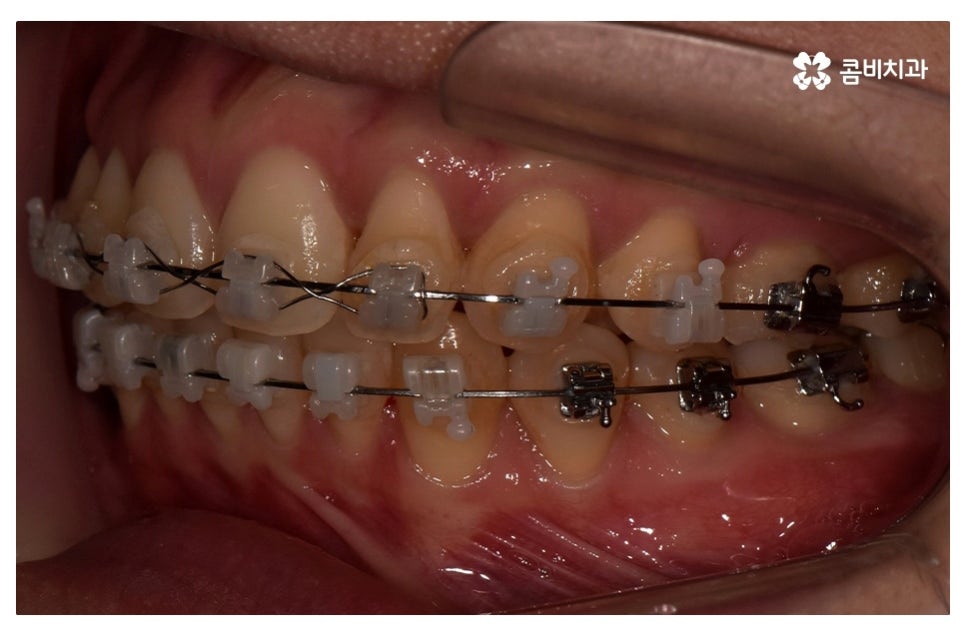

이번 포스팅에서 보인 덧니교정 사례의 경우 기능이 적은 작은 어금니를

발치하여 교정이 진행되었으며 발치를 진행하는 경우

작은 어금니를 발치하는데 충치 등으로 인해 손상이 큰 치아를

발치하는 경우가 일반적이라고 할 수 있어요.

요즘은 교정 장치의 선택에 있어서 다양한 선택이 가능하지만

보편적으로는 본 포스팅의 사례처럼 클리피씨 교정이 많이 선호되고 있어요.

클리피씨 교정은 일반적인 교정보다 치료 기간을 단축시킬 수 있고

통증이 비교적 적으며 세라믹 재질로 심미적이라는 장점이 있어요.

위 환자분의 경우 덧니교정에 걸린 치료 기간은 약 24개월 정도이며

성인 이후에 치료를 진행한 사례라고 볼 수 있어요.